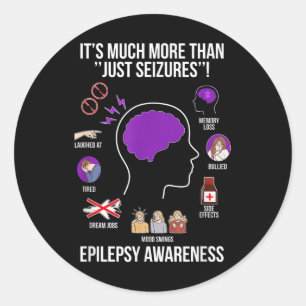

Sticker Rond Sensibilisation au cancer du cerveau _2

Prix13,40 $CA